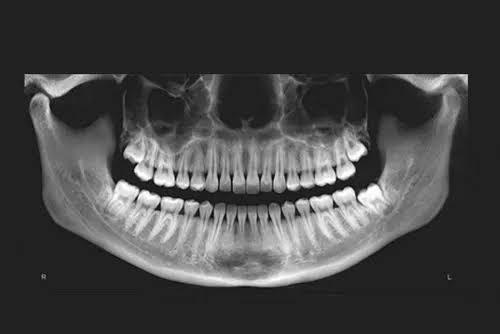

OPG (Orthopantomogram) X-rays play a vital role across various branches of dentistry by providing a comprehensive panoramic view of the entire oral cavity, including the teeth, jaws, and surrounding structures.